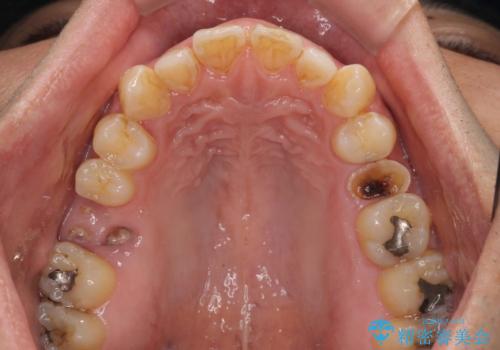

強い痛みのあった歯は、既に神経組織が失活しており根管治療が必要でした。

反対側の歯は、歯根だけが歯肉に埋もれて残っている状態のため、抜歯が必要な状態でした。

歯根だけとなっている歯はインプラントに、神経組織の失活している歯は根管治療を行い、いずれもオールセラミッククラウンにて補綴治療を行うこととしました。